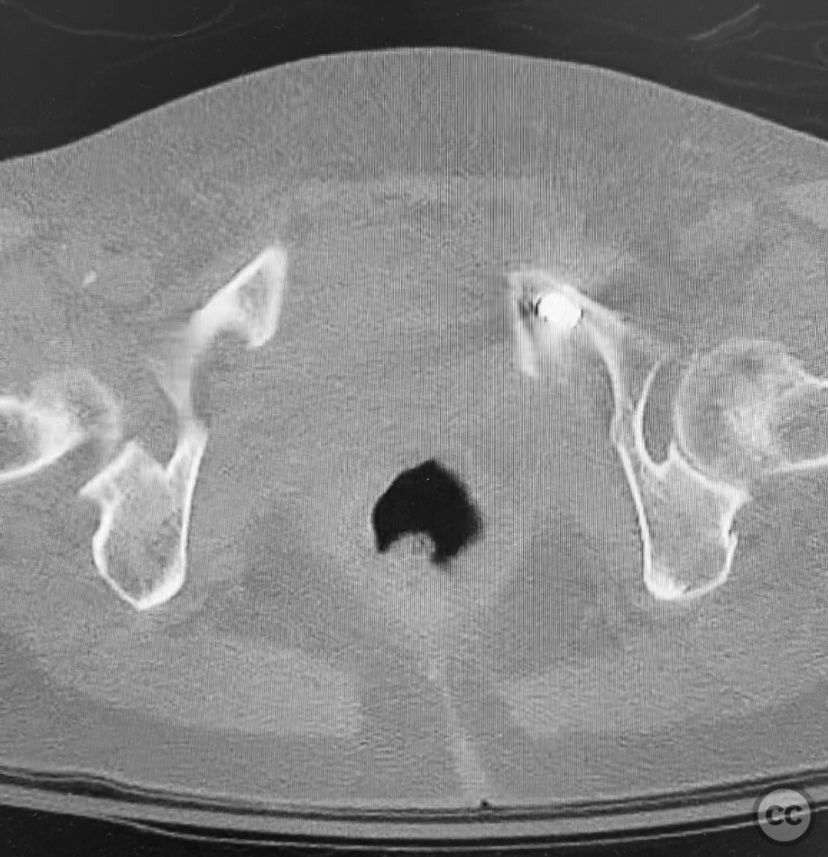

Clinical and radiological findings:  A 74-year-old female presented following a fall from standing height, unable to mobilize due to severe pelvic pain (9/10). Examination under anesthesia with fluoroscopic assessment (AP and inlet views) demonstrated instability and displacement of the pelvic ring with minimal manual compression at the iliac crests. Imaging revealed left-sided posterior iliac/sacral and pubic ramus fractures consistent with an AO/OTA 61-B2 (lateral compression type) pelvic ring injury. No neurovascular deficits were noted.

Planning remarks:  The preoperative plan involved closed reduction of the pelvic ring under fluoroscopic guidance, followed by percutaneous screw fixation of the left posterior iliac/sacral region and the ipsilateral pubic ramus. Detailed preoperative CT imaging was used to plan safe osseous corridors for screw placement, correlating with intraoperative fluoroscopic landmarks.

Orthopaedic implants used:   Cannulated iliosacral screw, cannulated pubic ramus screw